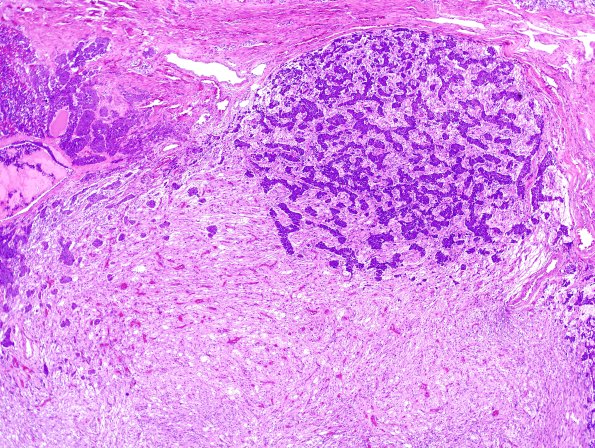

6C2 Pituitary, normal basophil invasion H&E 3

Increasing magnification of basophil invasion. (H&E)